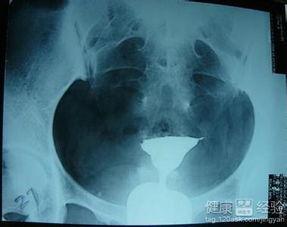

3. X光拍摄

在造影剂注入后,医生会使用X光设备拍摄你的腹部,以便观察输卵管是否通畅。这时,你可能会感到有点胀痛,但这是正常的生理反应。

4. 观察结果

拍摄完成后,医生会根据X光片的结果来判断你的输卵管是否通畅。如果输卵管通畅,造影剂会顺利通过;如果输卵管不通,造影剂可能会在某个地方停滞。